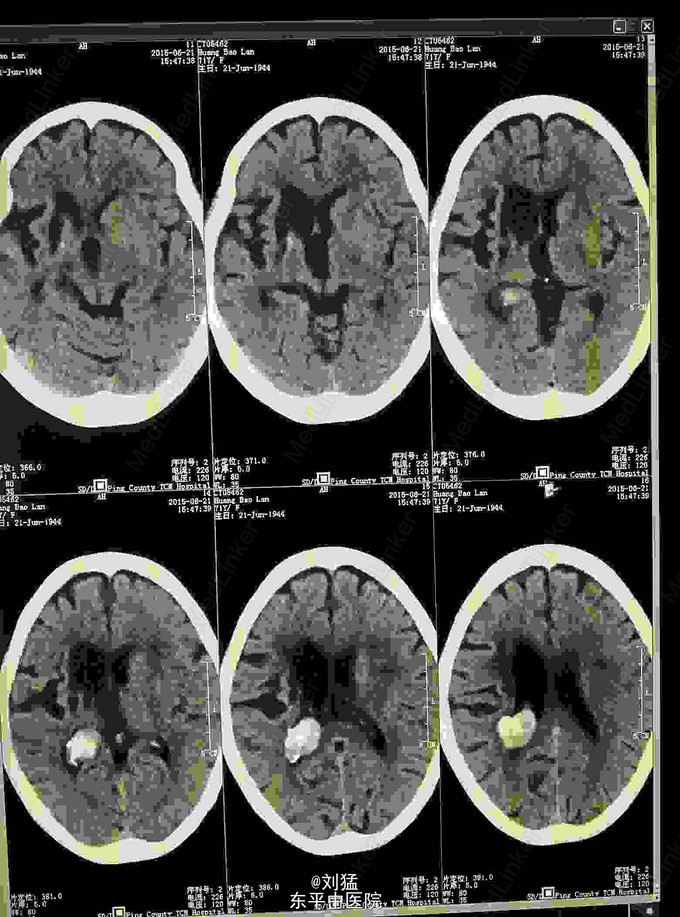

侧脑室病例 脑膜瘤?

脑膜瘤

患者女,71岁,查体发现

(左侧脑室)脑膜瘤

左侧脑室后角巨大脑膜瘤